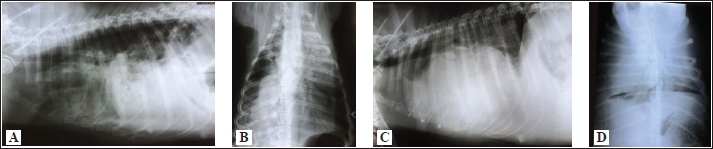

In 2 out of 40 dogs (2/40 dogs or 5% of dogs), radiographs could only be assessed subjectively. These two dogs had the most severe radiographic features in the areas of lung fields, which made it impossible to assess their cardiac silhouette and vascular pattern, either subjectively or objectively (Fig. 3A–D).

Fig. 3. Radiographs of two dogs with the most severe changes. 3A and B - LL and DV views of a 9-year-old female Rottweiler. Massive opacities can be seen in the ventral areas of the cranial, middle and accessory lobes (in LL view), and in the left cranial, right cranial and caudal and accessory lobes (in DV view). These changes cover the heart silhouette. Also, reduced flows to the left caudal and right middle lobes can be seen. In the caudal lobes in LL view, and in the right caudal lobes in DV view, air alveolograms can be seen. 3C and D - LL and DV views of a 5-year-old female mix-breed dog: Massive opacification in the ventral areas of lung lobes in LL view made it impossible to define the heart silhouette. The trachea lies almost parallel to the spine, with a mixed interstitial-alveolar pattern of the caudal lung lobes. On the DV view diffuse opacities in lung lobes prevent cardiac silhouette and vascular pattern assessment.

The radiographs of all other dogs were considered suitable for assessment both subjectively and objectively. Aside from 4 dogs, in which only LL were available, there were also two dogs in which opacity in their lung field in their DV radiographs enabled only the assessment of some subjective and objective parameters.